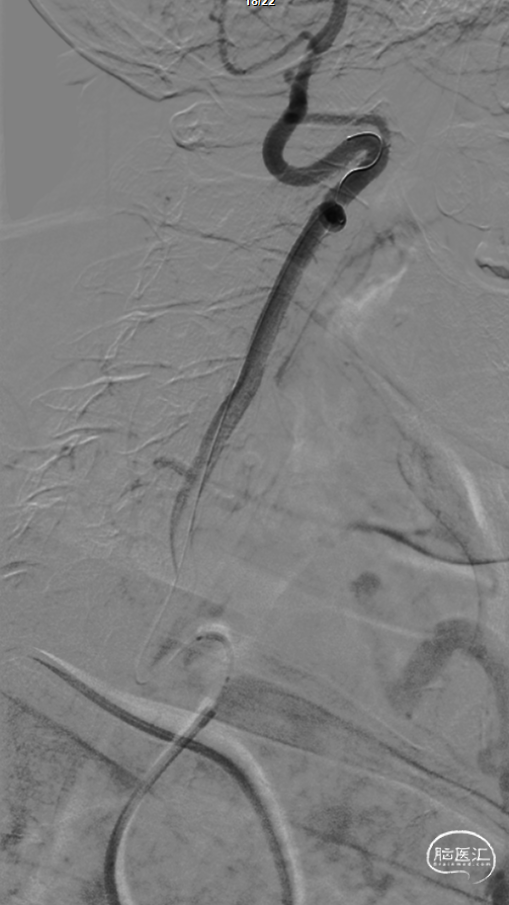

导引导管到位:

使用Simmons 2导管送达左侧锁骨下动脉,长泥鳅导丝超选左侧腋下动脉,交换撤出Simmons 2导管,送入SPB 3.5导引导管至左侧锁骨下动脉起始部。

微导丝到位:

在路图指引下将微导丝谨慎通过狭窄及V1迂曲段并留置于左侧椎动脉V3段远段。

操作要点:

1、微导丝塑形,使用双导丝技术

2、微导丝操控,谨慎通过狭窄段